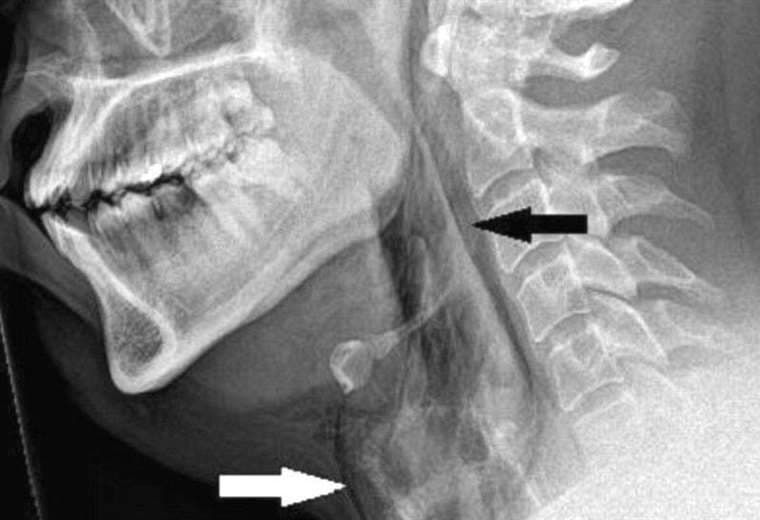

Las exploraciones revelaron que sufrió un desgarro de 2 mm en la tráquea.

Cuando los médicos examinaron al paciente, escucharon un crujido al tocarle el cuello y descubrieron que no tenía control de movimiento.